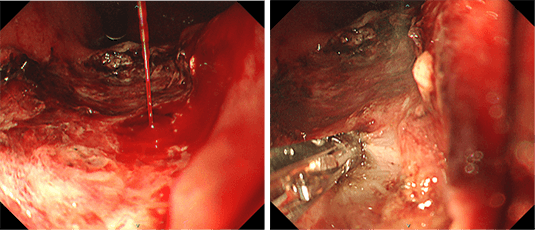

出血性胃潰瘍、食道静脈瘤破裂、大腸憩室出血などでは出血点を内視鏡で確認し、様々な処置具や薬剤を用いて止血します。また、限られた医療機関でしか行われていない「胃静脈瘤破裂に対するヒストアクリル硬化療法」も可能な体制を整えています。

出血性胃潰瘍に対する止血鉗子を用いた止血術

胃静脈瘤破裂に対する

ヒストアクリルを用いた止血術

大腸憩室出血に対するバンドを用いた結紮術